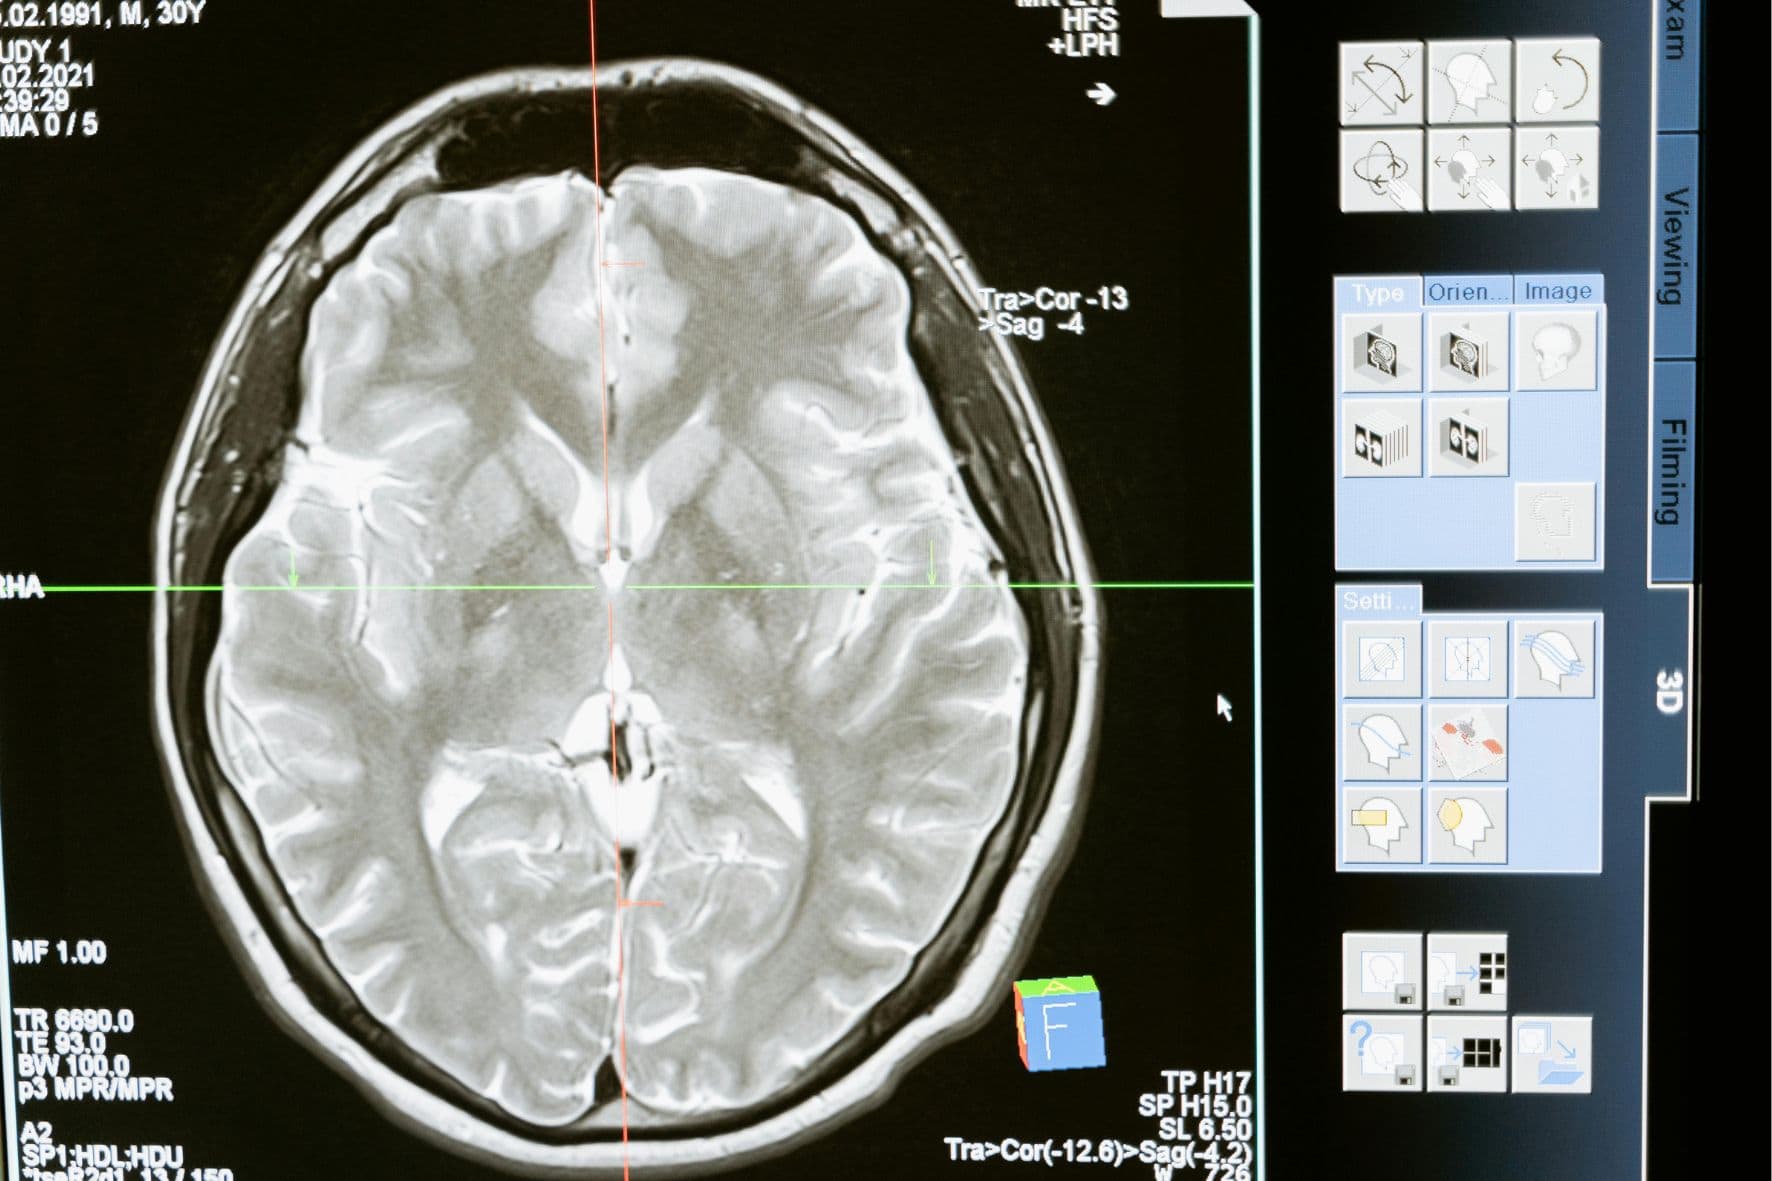

El glioblastoma es uno de los tumores más agresivos del sistema nervioso central. Se desarrolla a partir de astrocitos, células que dan soporte a las neuronas, y puede crecer a gran velocidad, destruyendo tejidos sanos en el camino. Sus síntomas, según la Mayo Clinic, incluyen dolores de cabeza persistentes, vómitos, convulsiones, trastornos del habla y la visión, e incluso dificultad para moverse o mantener el equilibrio.

A pesar de las múltiples investigaciones y tratamientos existentes, la expectativa de vida para quienes lo padecen sigue siendo baja: entre 12 y 16 meses tras el diagnóstico, incluso con intervención médica intensiva. La falta de avances reales se debe, en parte, al desconocimiento profundo de los mecanismos moleculares que impulsan el crecimiento de estos tumores.